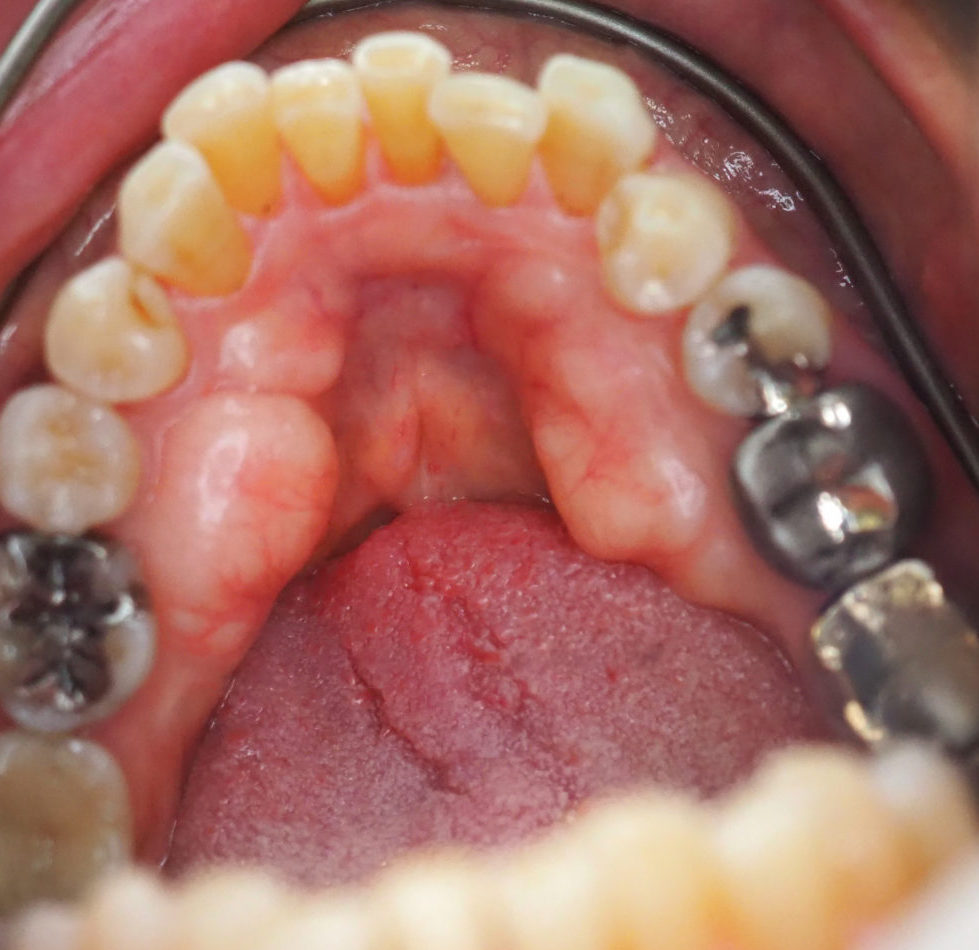

症例

当院でも骨隆起除去をおこなっておりますので気になる方はご相談ください。